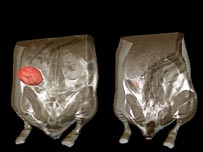

Imagens mostram que tumor encolheu em organismo de rato

Imagens mostram que um tumor encolheu em um organismo de rato

Experiências com animais de laboratório mostraram que mesmo que reativado brevemente, o gene reduz drasticamente o tamanho dos tumores, em alguns casos em até 100%.